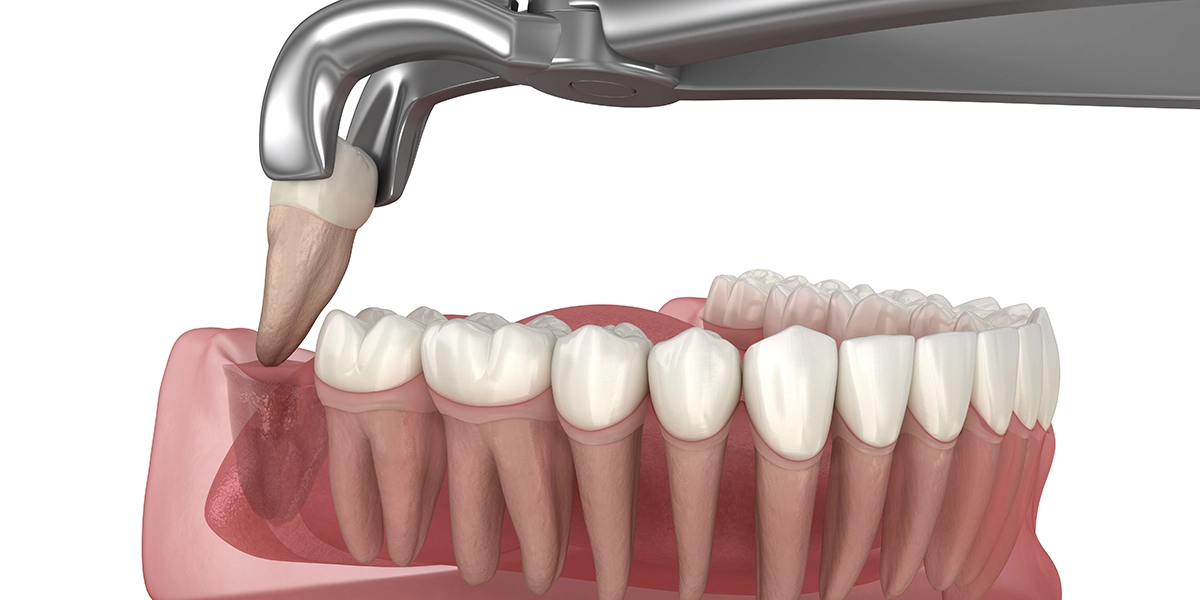

親知らずの抜歯は、生え方によって難易度が大きく異なります。

まっすぐ生えている親知らずであれば、通常の抜歯と同様に、麻酔をして器具で抜くだけで済みます。処置時間は10〜20分程度です。